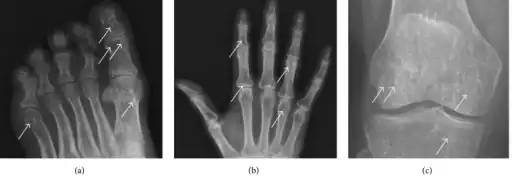

a-c)Osteopoikilosis in feet, hand, knee -

The radiographic appearance of osteopoikilosis on an X-ray is characterized by a pattern of numerous white densities of similar size spread throughout all the bones. This is a systemic condition. It must be differentiated from blastic metastasis, which can also present radiographically as white densities interspersed throughout bone. Blastic metastasis tends to present with larger and more irregular densities in less of a uniform pattern. Another differentiating factor is age, with blastic metastasis mostly affecting older people, and osteopoikilosis being found in people 20 years of age and younger.

In terms of the diagnosis Osteopoikilosis is radiographically evaluated via the presence of multiple symmetrical circular sclerotic opacities [2]

The distribution is variable, though it does not tend to affect the ribs, spine, or skull.[3]